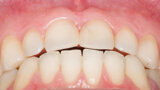

Fig. 6: Functional analysis wax-up.